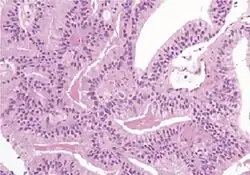

Acinar adenocarcinoma

These constitute 93% of prostate cancers.[2]

Microscopic characteristics